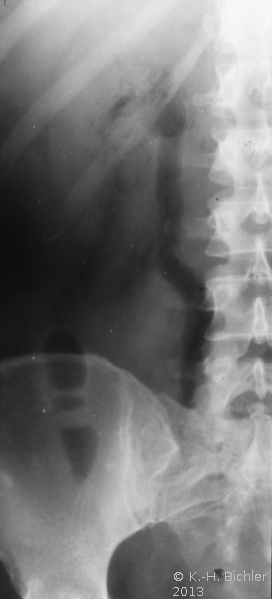

- Abbildung Harnleiterkarzinom (Urothel) links Mitte:

- a) Ausscheidungsurogramm: Abbruch der "Kontrastmittelstraße"